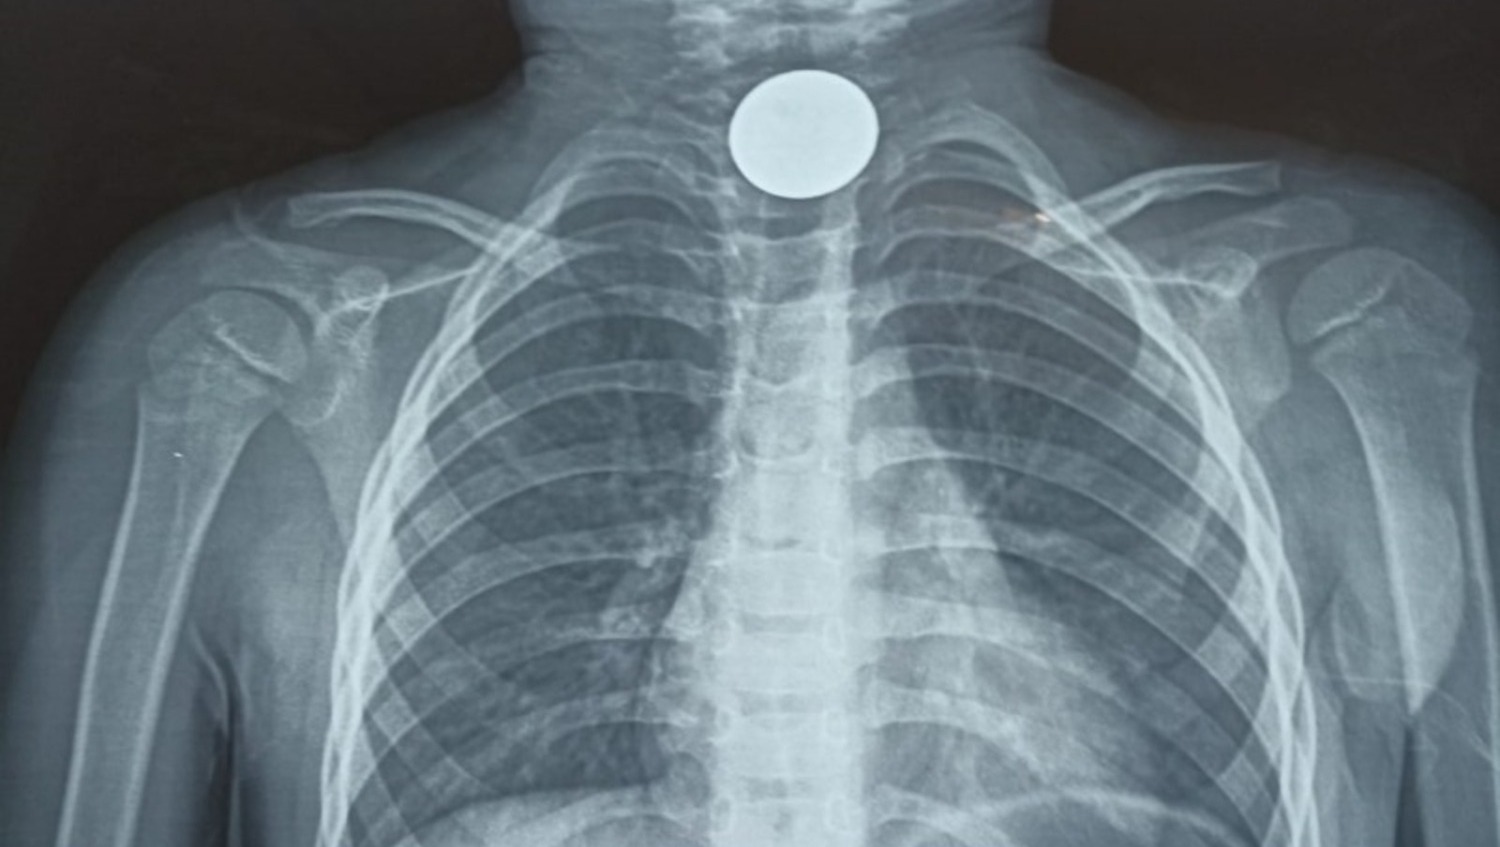

В Башкирии в сентябре подросток во сне проглотила беспроводной наушник. 15-летняя пациентка в экстренном порядке поступила в больницу скорой медицинской помощи. Выяснилось, что вечером девушка заснула с беспроводным наушником в ухе. Ночью проснулась из-за боли в горле. В этот момент она обнаружила, что наушника рядом с ней нет, разбудила родителей и они вызвали скорую помощь. Пациентку доставили в больницу скорой медпомощи, где сделали рентген брюшной полости и фиброгастроскопию, обследовав пищевод, желудок и 12-перстную кишку. Наушник был обнаружен в кишечнике. Девушку госпитализировали в отделение детской хирургии. В этом случае все обошлось без оперативного вмешательства. Предмет вышел из организма естественным путем, без осложнений.